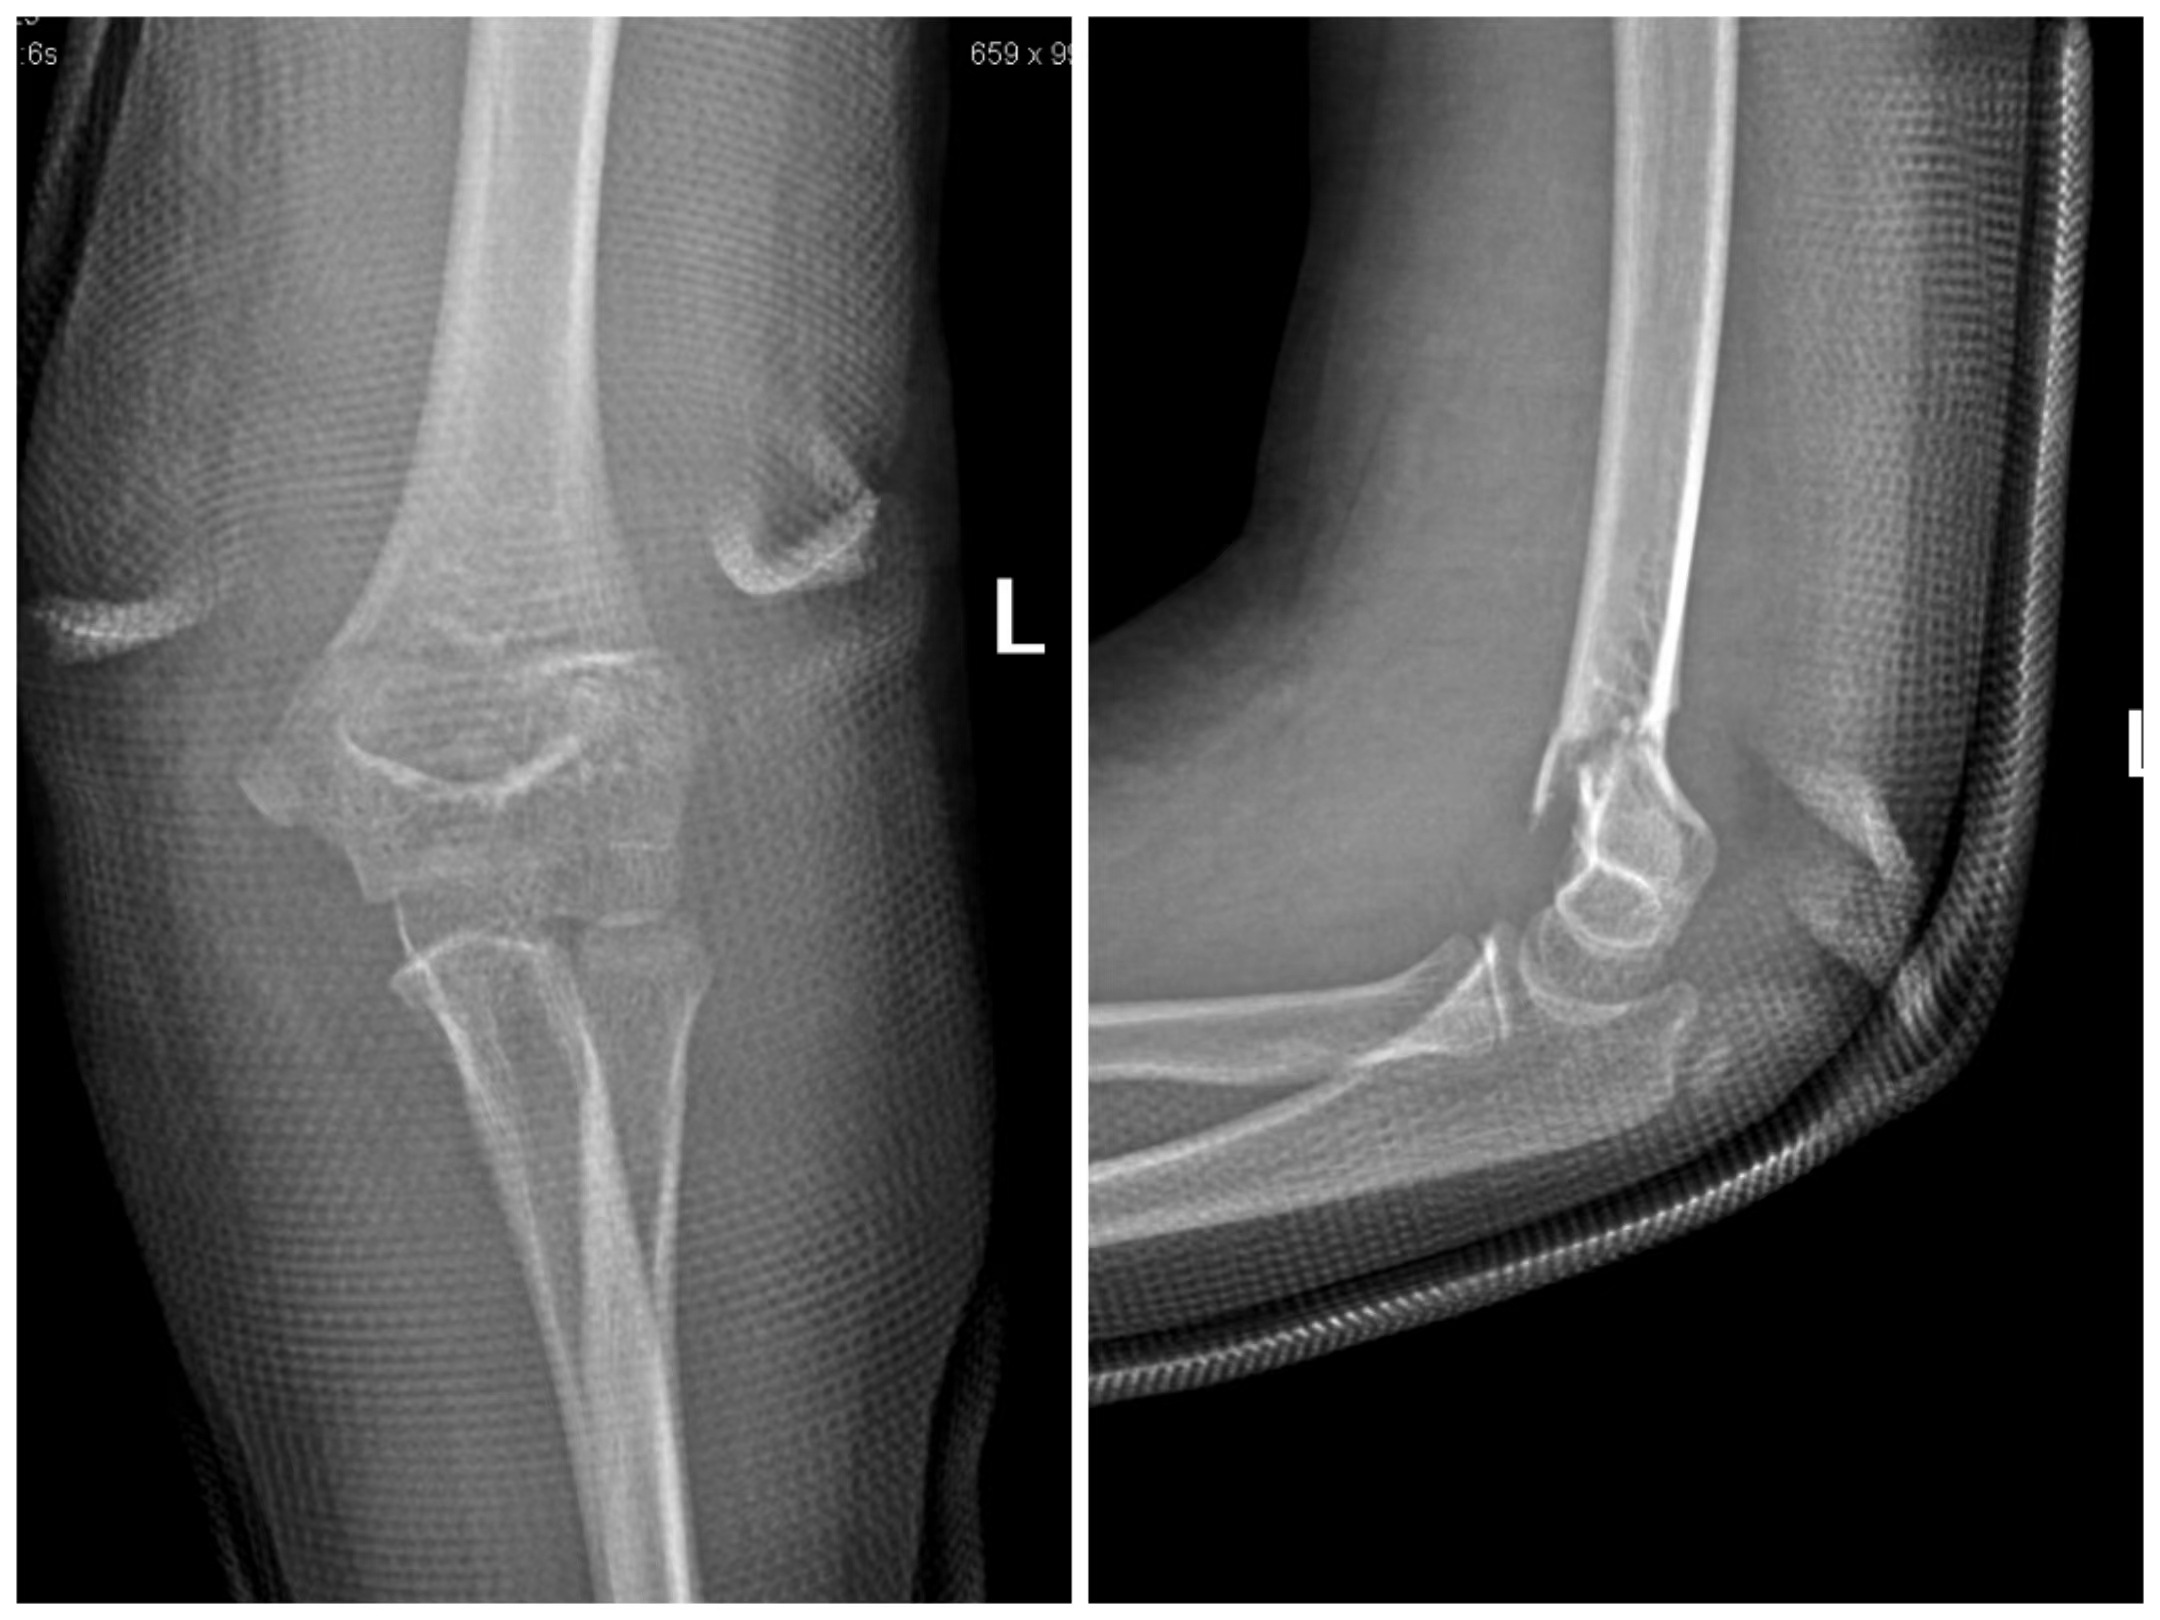

肱骨髁上骨折需要手术治疗吗?医生通常会根据儿童的骨折类型进行判断,通常我们将肱骨髁上分为4型( Gartland分型 ),即Ⅰ型:无移位;Ⅱ型:部分移位,后侧皮质相连;Ⅲ型:完全移位;Ⅳ型:伸直不稳定或屈曲型,尺侧塌陷型。Ⅰ型多采用保守治疗,Ⅲ型、Ⅳ型采用手术治疗,Ⅱ型介于两者之间,目前多倾向于手术治疗。

Gartland Ⅱ型

Gartland Ⅲ型

Gartland Ⅳ型